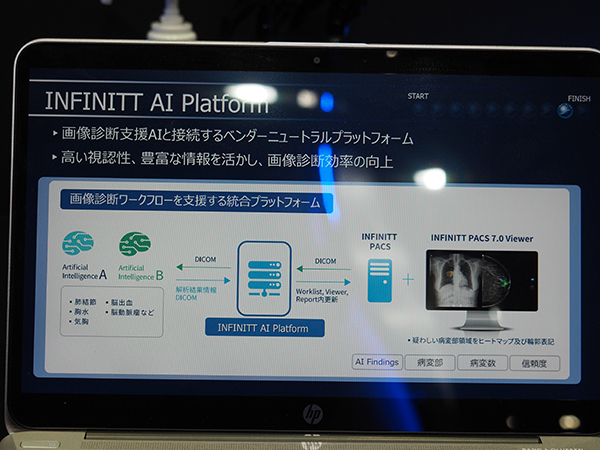

主力製品である高機能・高品質PACSビューア「INFINITT PACS 7.0」は,人工知能(AI)技術を活用した画像解析支援ソリューションとシームレスに連携し,リアルタイムで解析情報を表示する“INFINITT AI Platform”を提供する。

ベンダーニュートラルな“INFINITT AI Platform”